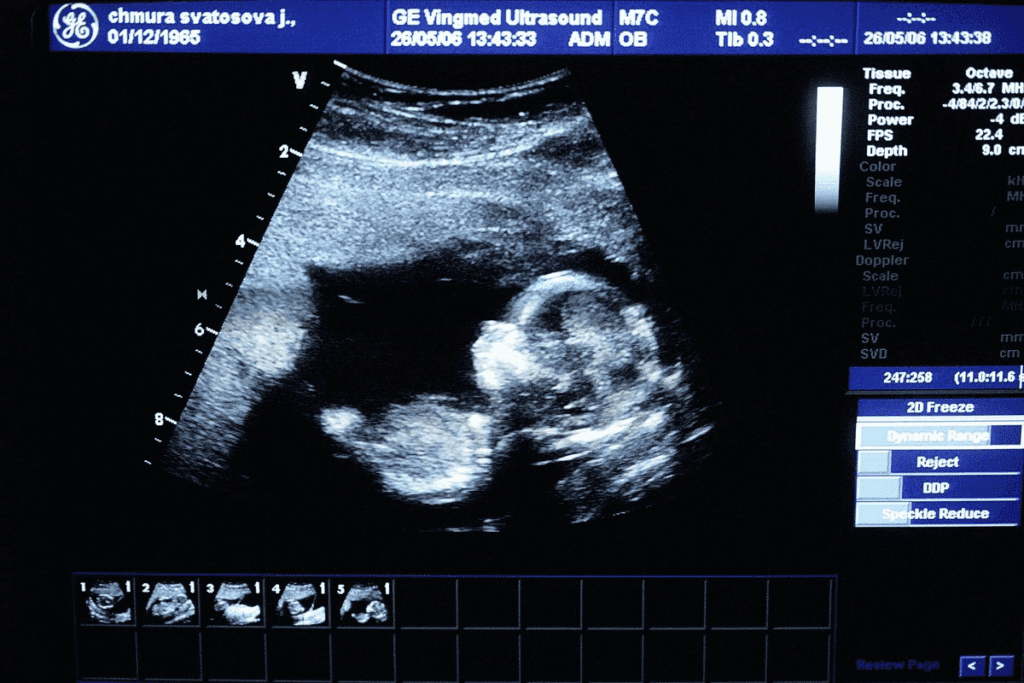

What Can Be Detected on Ultrasound at 4 Weeks

Ultrasound technology lets us see early signs of pregnancy, like the gestational sac at 4 weeks. The embryo is tiny, but we can spot some parts on an ultrasound.

The Gestational Sac Appearance

The gestational sac is one of the first things we see on an ultrasound at 4 weeks. It looks like a small circle in the uterus. Seeing the gestational sac is a key sign of early pregnancy and usually happens by the fourth or fifth week.

When First Ultrasounds Are Typically Performed

Ultrasounds can be done early, but they’re not always needed at 4 weeks. The first ultrasound, or dating scan, usually happens between 6 to 9 weeks. But, sometimes an ultrasound is done earlier to check on the pregnancy or to address any worries.

What Cannot Yet Be Seen at This Stage

At 4 weeks, we can see the gestational sac, but not the embryo or its heartbeat. The embryo is too small, and it’s just starting to grow. As the pregnancy goes on, we’ll see more details on ultrasounds.

To sum up, at 4 weeks, an ultrasound can spot the gestational sac, a sign of pregnancy. Ultrasounds aren’t always done at this time, but they can be helpful. As the pregnancy gets further along, we’ll see more about the embryo’s growth on future ultrasounds.